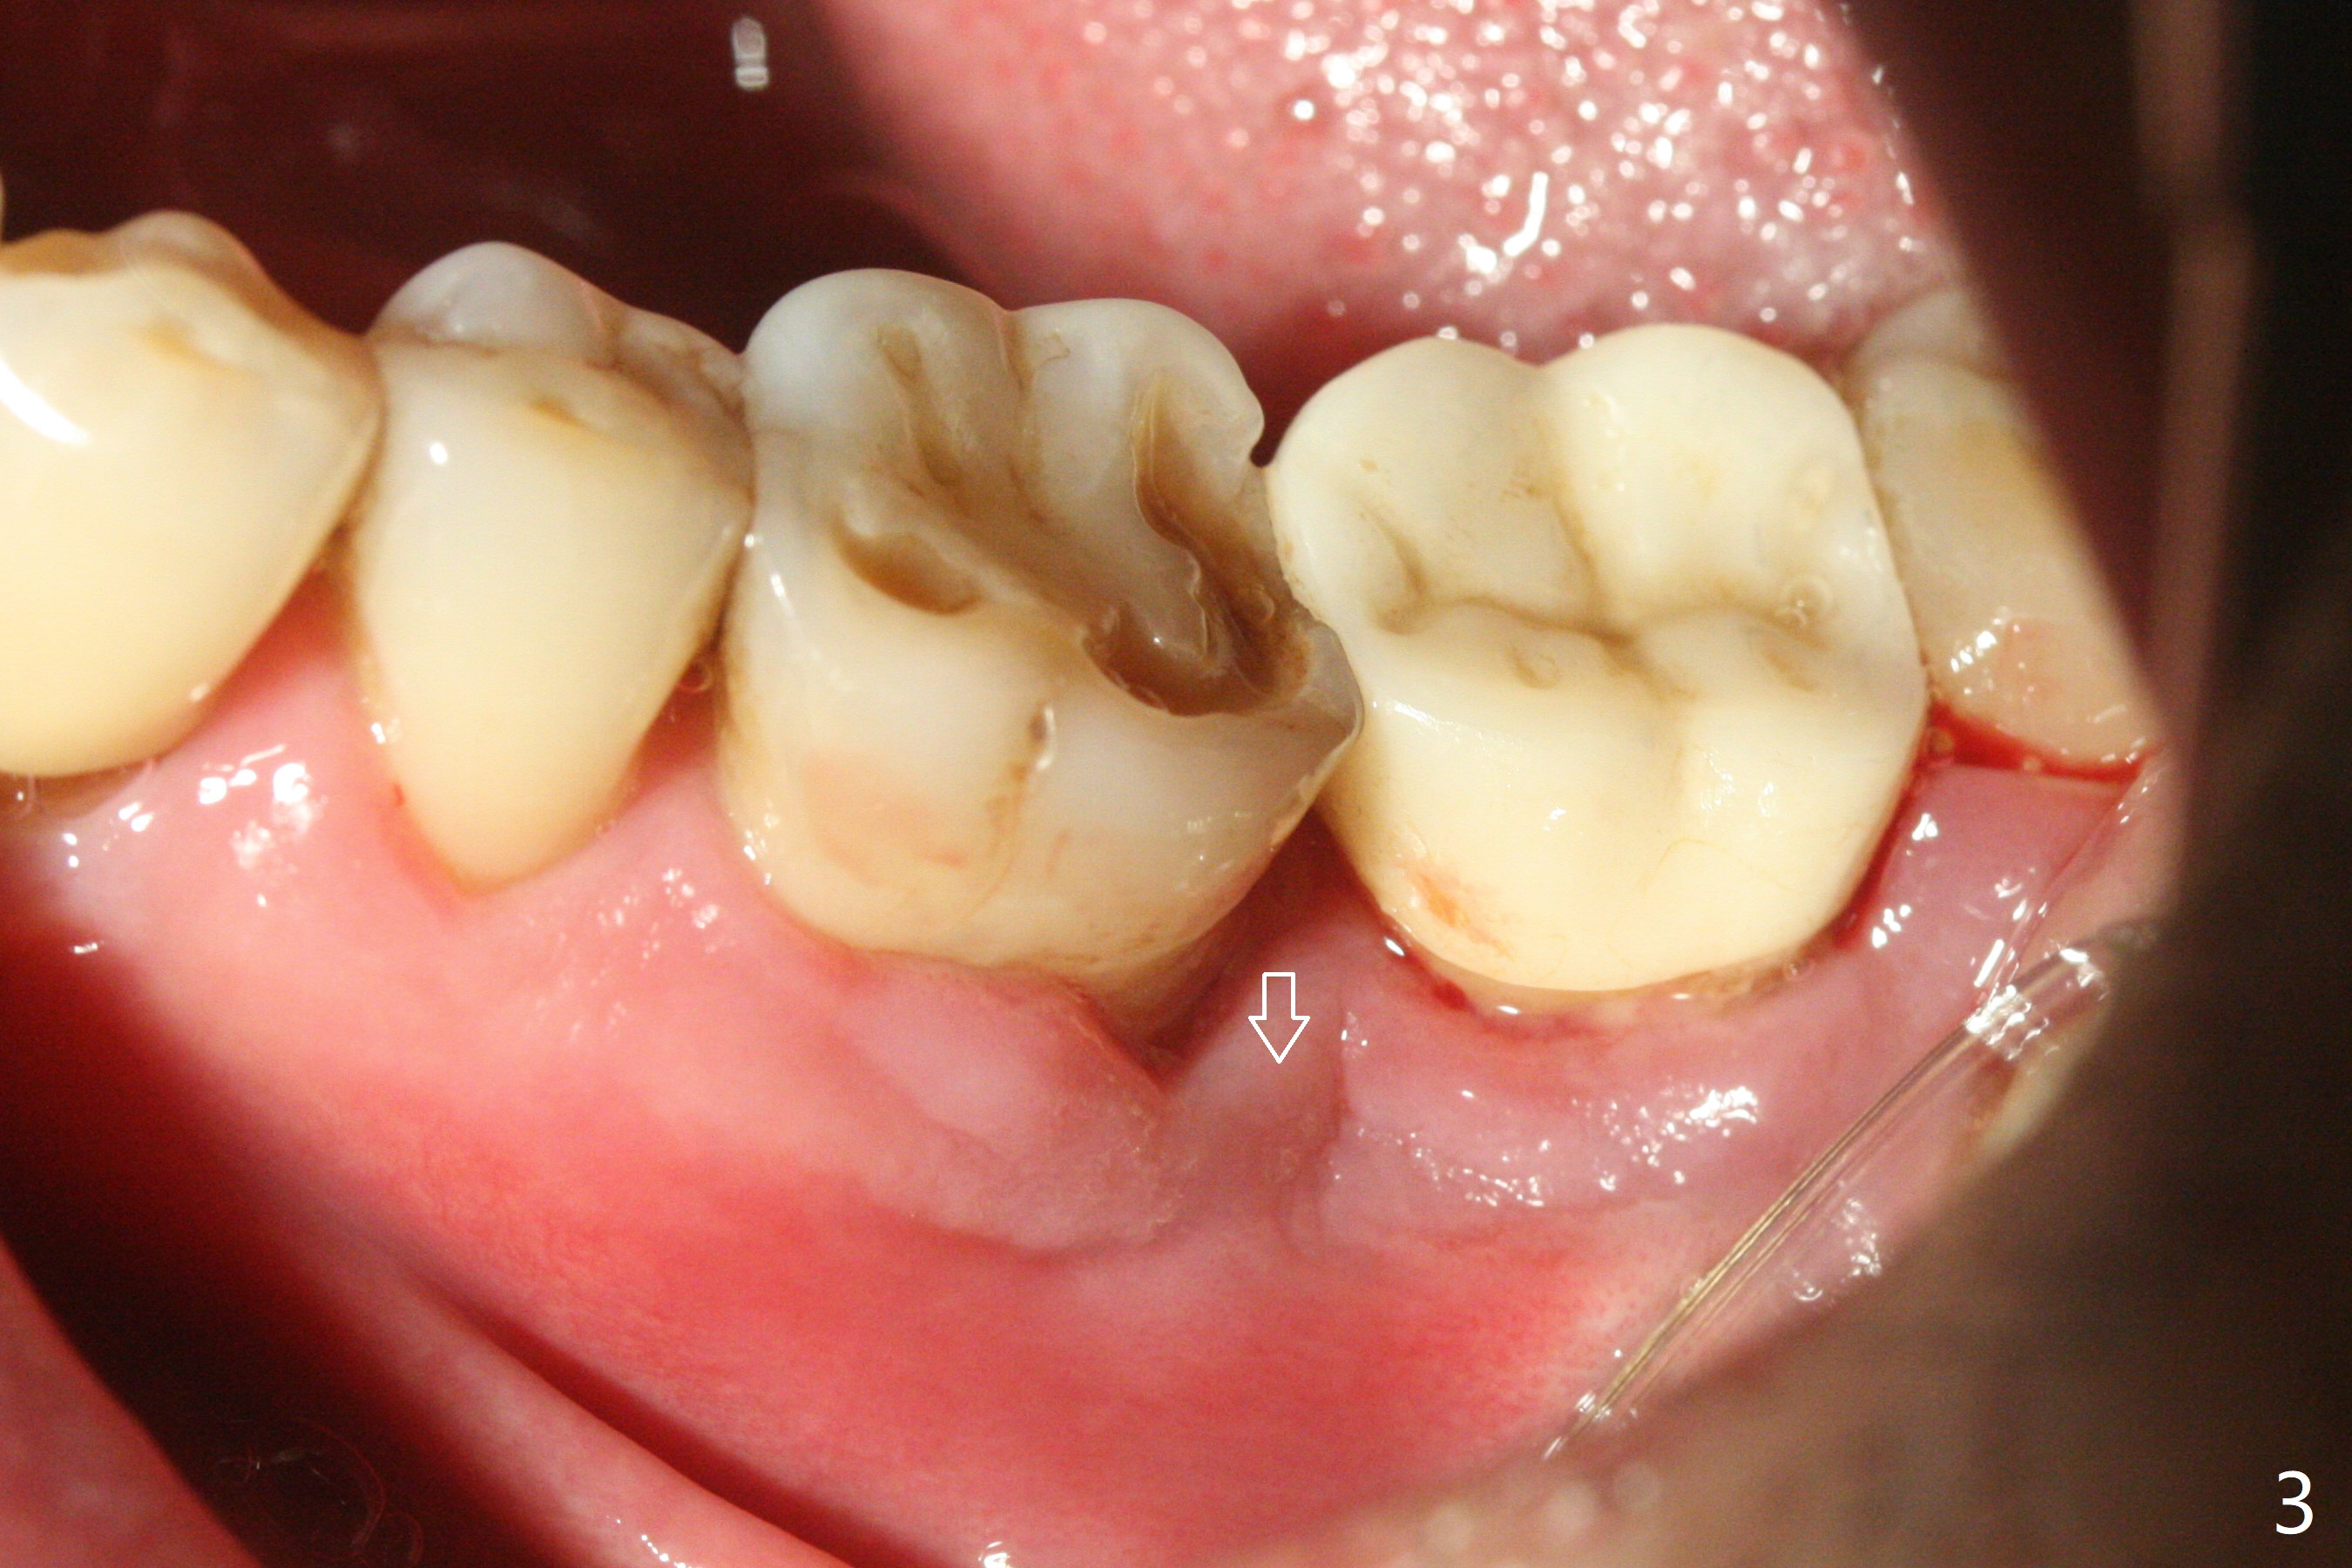

54岁男牙齿问题好像与牙周病和咀嚼力大有关(图一),虽然右上3(图二)和左下6(图三,四)需要治疗,因为疼痛他要求先处理左上6(图五)。后者腭侧根骨质吸收严重,植体尽量颊侧植入(图六),4.5 或者5.0x11毫米。放置粘性骨粉至植体平台,为了简化术中基台放置,使用Non-Hex Temporary Abutment,临时牙冠做的尽量大,占据牙槽窝空间,最后将PRF膜塞入两者之间。Return to Prevent Molar Periimplantitis (Protocols, Table) No Deviation No Caries Metronidazole CT/前牙植牙 Socket Shield Xin Wei, DDS, PhD, MS 1st edition 10/11/2020, last revision 02/21/2021